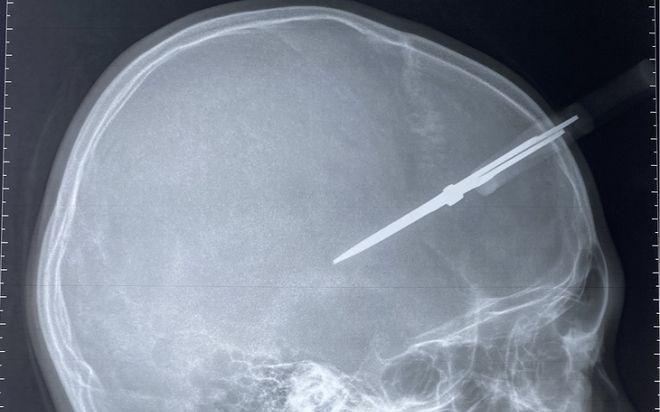

Trước ngày nghỉ Tết, bé trai bị kéo đâm thủng hộp sọ khi đang chơi đùa trong lớp

Gia đình cho biết trong buổi học cuối cùng trước khi nghỉ Tết, bé H. chơi đùa với bạn cùng lớp và vô tình bị kéo đâm vào đầu